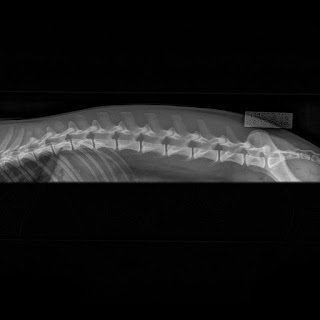

Laran selkä oli ikäisekseen oikein siisti, lonkat tiiviit ja epävirallisesti A/A. Ristiluun keskiharjanne katkeaa S1-S2 välissä, jonka vuoksi lausuttiin LTV1.

Innan selkä on nyt veteraani-ikäisenä oireillut erityisesti kylmällä, joten suuri yllätys oli että sen selkä oli kaikilta osin priimaa. Lonkat myös epävirallisesti A/A.

Empulla on S1 nikama hiukan matalampi kuin muut, lisäksi 1. häntänikama luutunut osaksi ristiluuta. Sillä on myös L1:ssä ylimääräiset kylkiluut. Lonkat epävirallisesti A/A, selkä lähti LTV2 VA1 mutta Kennelliiton lausunnossa LTV1 VA0. Luotan enemmän kuvaajan ammattitaitoon, ja pääasia kai on että itse tiedän mitä selässä on.

Sitten se viimeinen yllätys. Ellalta löytyi hyvin selkeä epäsymmetrinen LTV3, mutta vaikka tuo S1 onkin ihan vino, sen lantio on kuitenkin kokonaisuudessaan suora. Sillä ei ole tuo S1 luutunut oikein, vaan se on 8. lannenikama, ja sitten vuorostaan 1. häntänikama on silläkin luutunut osaksi ristiluuta. Tämä näkyy hyvin selkeänä sivukuvassa. Lisäksi löytyi ylimääräiset kylkiluut, josta kuvaajan arvio VA1. Lonkat kuitenkin siistit ja tiiviit, epävirallisesti A/A. Ellan lausunto LTV3 VA0, eli silläkin oli jätetty nuo muutokset huomiotta.

Tämä oli siinä mielessä suuri yllätys, että Ella ei viime kesän kivikovalla Kartanon radalla juostuja startteja lukuun ottamatta ole koskaan tuota selkäänsä oireillut, mikä on tietysti erittäin hyvä asia. Se on kuitenkin juossut kilpaa 4 kautta, vaikkakin kiimat sotkivat etenkin viime ja edellisellä kaudella aika pahasti. Itselle tämä oli ihan hyvä bitch slap, sitä kuvittelee omista koiristaan kaikenlaista mutta totuus voikin sitten olla toinen - kumpaankin suuntaan. Töissä kylläkin näen viikoittain terveeksi kuvattuja oireilevia koiria, sen sijaan huomattavasti vähemmän on niitä, kellä nämä muutokset tuottaisivat vastaavia ongelmia. Ennen seuraavan pentueen suunnittelua koko Volbeat-porukka käy kuitenkin kuvissa, ja vasta sitten mietin asiaa eteenpäin. Selkämuutosten periytyvyys ei tosin ole ihan niin selvää, huonoista voi tulla priimaa ja sitten taas terveeksi kuvatuista voi tulla sutta ja sekundaa.